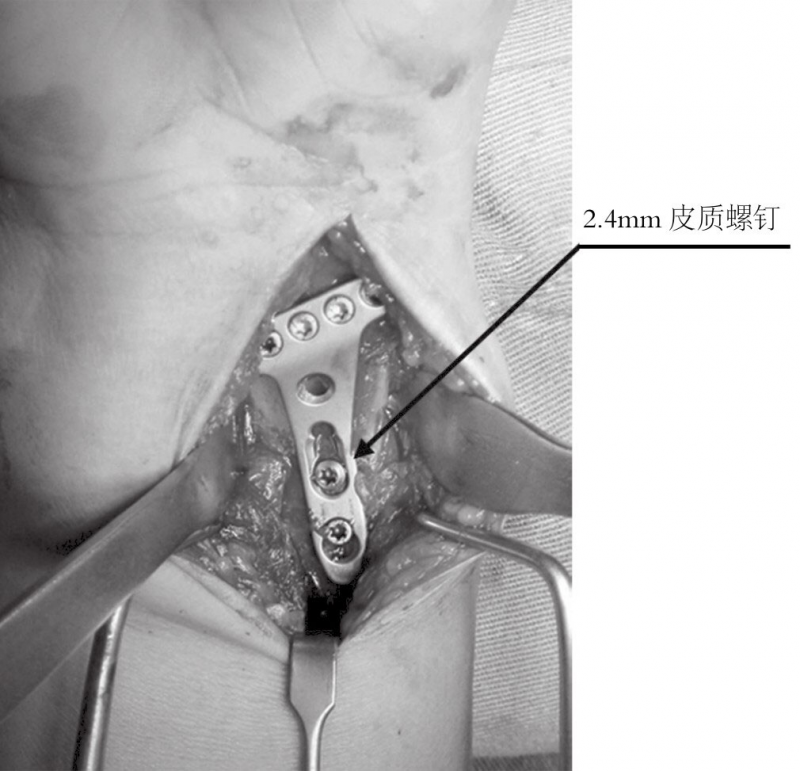

远端的锁定螺钉首先置入。接着用一枚普通的2.4mm皮质螺钉置入,将钢板贴向桡骨远端骨面。

由于有远端固定角度的锁定螺钉,钢板紧贴桡骨干能够增加桡骨远端关节面的倾斜度,所以要选用最靠近桡骨干的螺钉孔置入头侧锁定螺钉(图5)。

图5 最后复位和骨折的固定